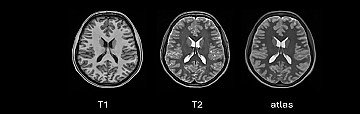

BDSLab Group, awarded for developing tools to support brain tumour treatment planning | ITACA Institute